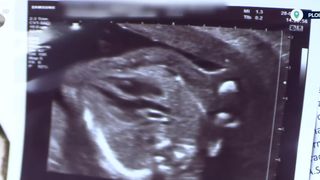

„Maternitatea din Ploiești e în mijlocul unui scandal șocant. O mamă de 34 de ani, care aștepta al treilea copil, spune că a fost informată de medici că poartă în burtă un făt mort. De fapt, ea l-ar fi văzut mișcând chiar în mâinile cadrelor medicale, care ar fi intervenit cu întârziere.

Tânăra de 34 de ani a ajuns pe 9 iulie la spital. Aștepta al treilea copil, dar totul s-a transformat într-un coșmar. I s-a comunicat că suferise un avort spontan la aproape 6 luni de sarcină, iar fătul nu se dezvoltase corespunzător. Femeia are însă o ipoteză șocantă. Spune că ar fi văzut cum fătul se mișca și ar fi așteptat așa minute sosirea cadrelor medicale.

„Șanse a avut și când au venit ele, deoarece copilul a mișcat. Îl țineau în mâini, copilul a mișcat picioarele. Eu le spuneam mereu: „Copilul meu mișcă!”. Ele nu și nu, o susțineau pe a lor, că e mort”, a spus Marilena Olteanu, pacientă.